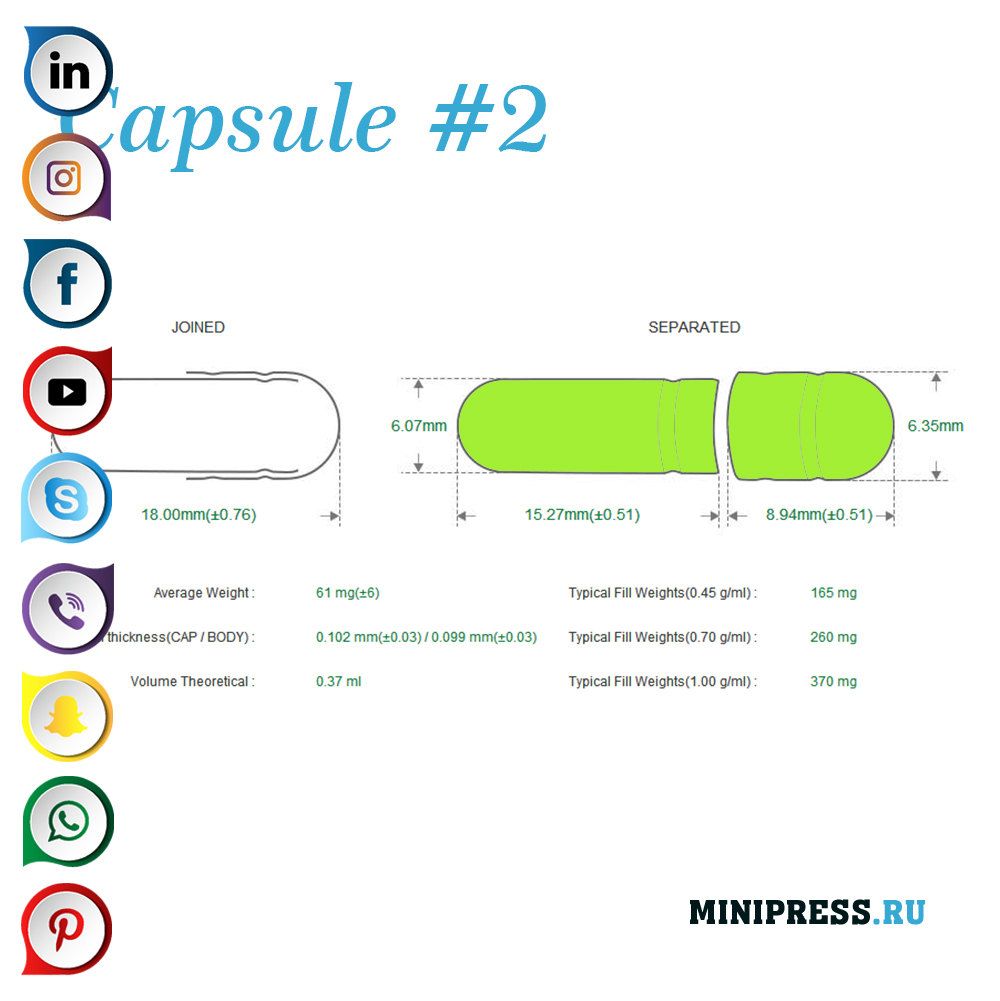

Velike zelatinskih kapsula: 000,00,0,1,2,3,4,5, A, B, C, D, E.